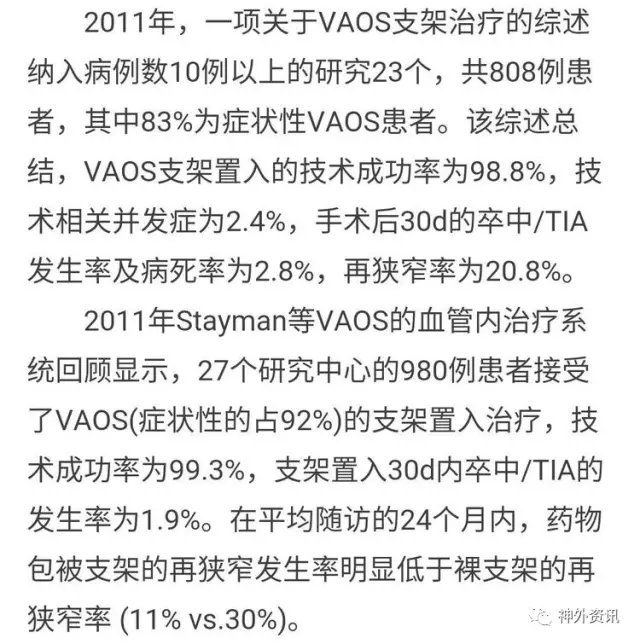

2014版VA狭窄指南:椎A开口狭窄在心脑血管病高发人群中可达50%,这么高的比例还是要高度重视,临床上TCD、CTA/MRA确可诊断。

2014版VA狭窄指南:文献提示VA支架后再狭窄达11-30%,所以VA内膜剥脱术对于症状性闭塞和狭窄还有技术应用的空间。

2014版VA狭窄指南:VA再狭窄目前认为主要与开口段狭窄段的长度有一定正√相关,与支架种类、扩张压力、局部开口段迂曲度有一定相关性。

2014版VA狭窄指南:外科治疗VA狭窄并非一线干预方法,但我们可以给支架植入失败和症状性支架内再狭窄或闭塞患者提供终极治疗方案,面对病人我们应当提供序贯性的治疗,天下大同,内外一家,解决的病人疾病之苦痛。